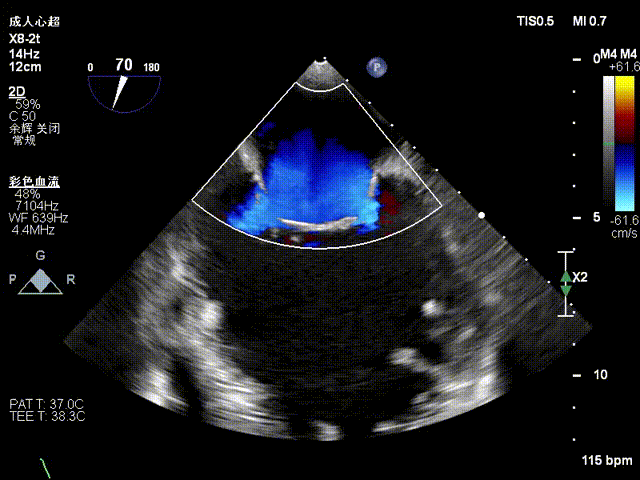

术前Commissural 切面

术前X-plane

术前X-plane上彩

1、1区到3区多中央反流束组成的宽度超过25mm的巨大反流束,需要评估多夹治疗可能;